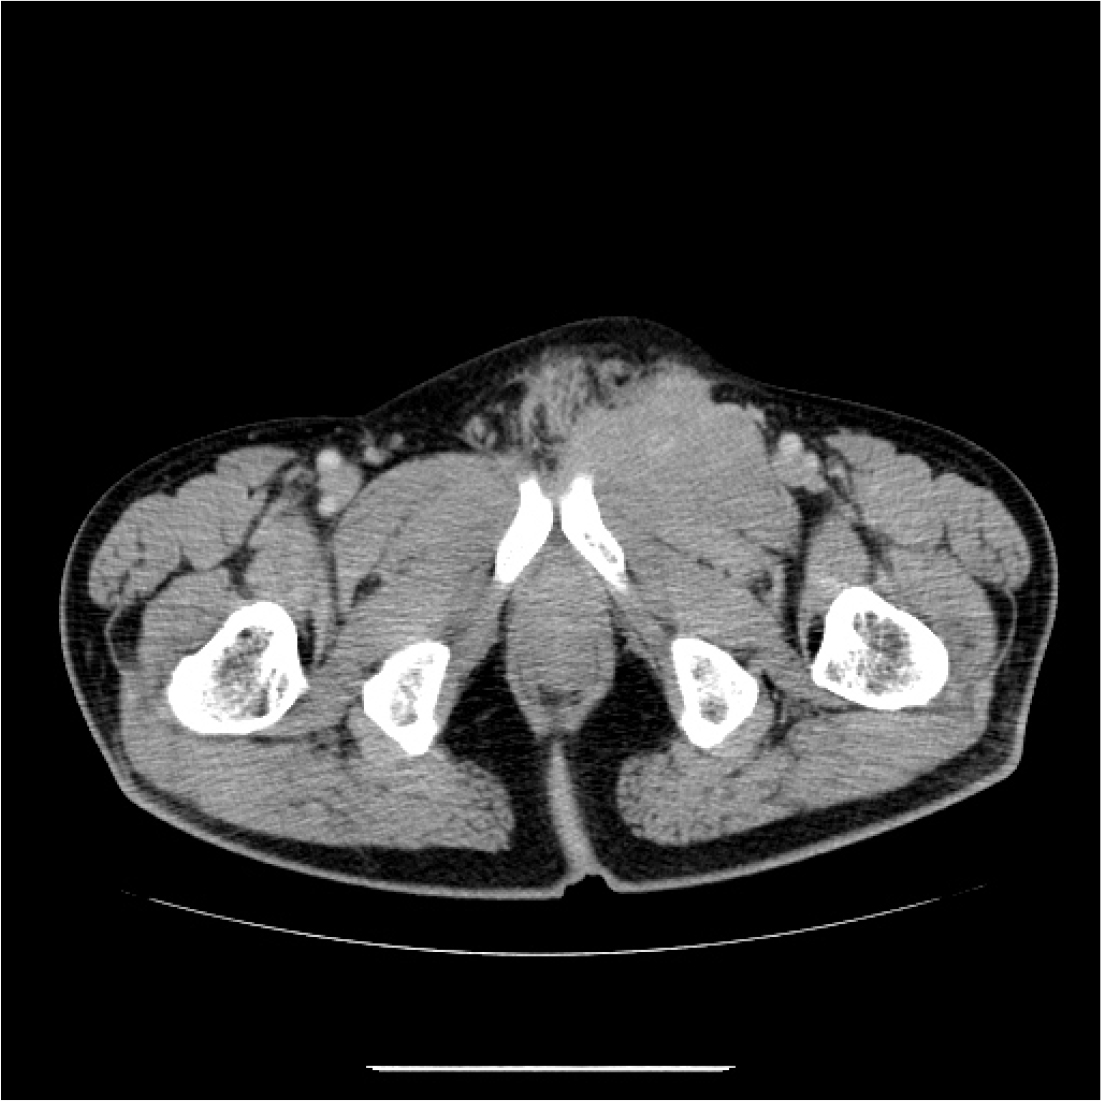

[그림 2] Pelvic CT에서 좌측 서혜부에서 치골 전방부위의 불규칙한 조영증강을 보이는 10 cm × 5 cm 크기의 연부 조직 종물이 관찰되었다.